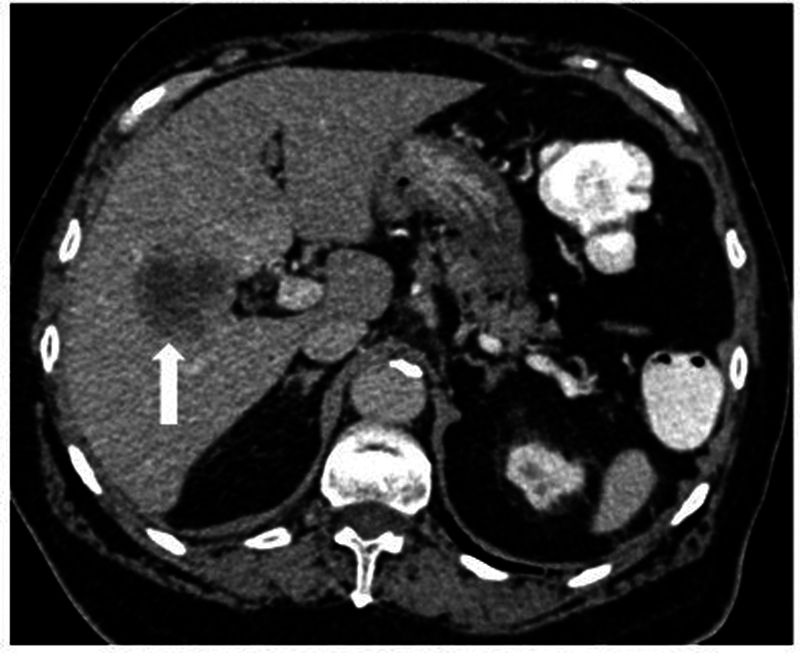

本文综述了计算机断层扫描(CT)、CT结肠镜检查(CTC)和磁共振成像(MRI)在结直肠癌的诊断、分期、疗效评估和随访中的作用。对于CT扫描,需要事先进行肠道准备。这是通过使用口服或直肠造影剂来增强结肠成像。像空气或二氧化碳之类的阴性对比有助于通过扩张结肠来检测息肉和肿块。虚拟结肠镜检查为息肉和癌症的检测提供了一种低辐射的选择。动脉和静脉相CT图像的静脉造影剂管理对于已知结肠癌病例的完全分期和残留/复发疾病的评估也很重要。对于MRI来说,多平面的高分辨率t2加权图像很重要,弥散加权成像(DWI)序列对重新定位很重要。一般不推荐静脉造影剂。对比增强CT和MRI用于淋巴结和远处转移分期,特别注意盆腔侧壁淋巴结。如果发现不明确或怀疑复发,应考虑进行正电子发射断层扫描(PET) CT进一步评估。

The present review highlights the role of computed tomography (CT), CT colonography (CTC), and magnetic resonance imaging (MRI) in the diagnosis, staging, response evaluation, and follow-up of colorectal cancer. For a CT scan, prior bowel preparation is required. This is done to enhance imaging of the colon with the use of oral or rectal contrast agents. Negative contrast like air or carbon dioxide are helpful in detecting polyps and masses by distending the colon. Virtual colonoscopy offers a lower-radiation alternative for polyp and cancer detection. Intravenous contrast administration with arterial and venous phase CT images is also important in complete staging of a known case of colon cancer and for evaluation of residual/recurrent disease. With respect to MRI, high-resolution T2-weighted images in multiple planes are important, with diffusion-weighted imaging (DWI) sequences being important for restaging. Intravenous contrast is not generally recommended. Contrast-enhanced CT and MRI are used for nodal and distant metastasis staging, with special attention to the pelvic side wall nodes. Positron emission tomography (PET) CT is to be considered for further evaluation if the findings are unclear and recurrence is suspected.